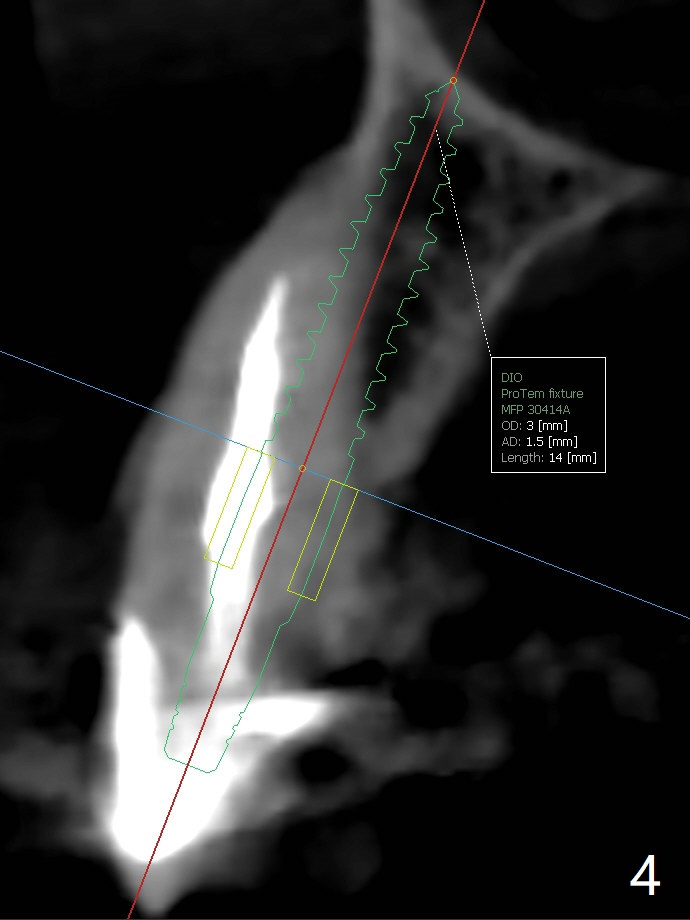

60岁女比较瘦小,8个月前因右下4,5轻度植体周围炎(4.5毫米软组织水平两段式植体种得太颊侧)就诊,准备重做,后来由于口腔卫生改善,症状减轻,她不愿意手术。右下6种植两个2.5x10毫米一段式种植。最近右上尖牙折裂,部分龈下(图一),她果断选择拔除种植。根尖片显示足够空间植入4.5x20毫米软组织水平植体(图二)。8个月前拍摄CT冠状面表明有充分根尖骨质(图三),植入3x14毫米骨水平一段式植体,便有2毫米颊侧,腭侧骨壁(减少植体周围炎可能性),而且修复角度优越(图四)。我可能在腭侧牙槽窝下1/3骨壁垂直钻入,然后改变钻洞方向,如红线,临床上,由咬合关系决定方位。如果不行,我有15度一段式植体。Bendable植体来不及买了。